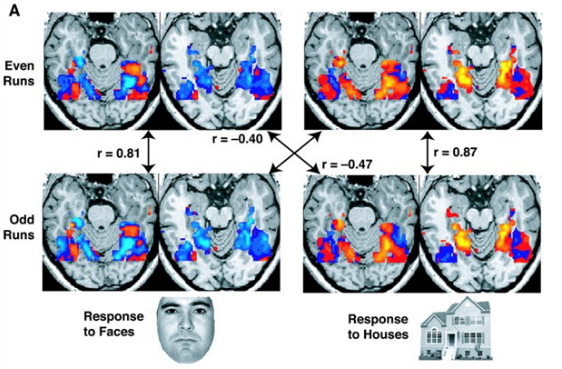

一项研究的fMRI图像显示,在看房子时,大脑的部分区域被激活,

看到人脸时,大脑的其他部分被激活。"r"值是相关性,正或负值越高表示匹配越好。